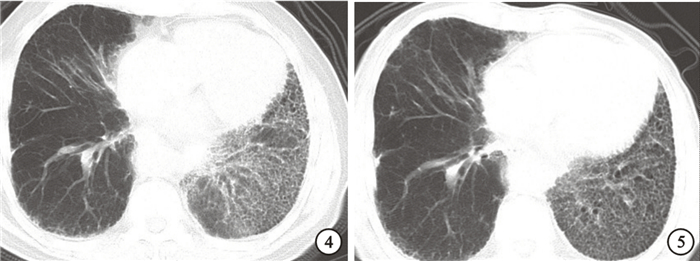

5年的隨訪期間,患者的血清CA19-9水平逐漸升高,而胸部CT的網格狀改變增多,并伴有靜息狀態、不吸氧情況下PaO2下降。結果見表 1和圖 1~5。

CA19-9在肺間質纖維化中異常表達的機制目前仍不清楚,可能機制有以下幾點:(1)?與CA19-9對中性粒細胞有趨化作用有關[5]。在特發性肺纖維化患者中血清中CA19-9升高的原因有可能為持續的上皮細胞損傷,下呼吸道中性粒細胞的聚集導致血管通透性改變,從而使CA19-9釋放入血[6]。CEA對中性粒細胞有趨化作用[7]。但是我們的隨訪及回顧性分析沒有發現在特發性肺纖維化患者血清中CEA升高的情況,表明CA19-9能更敏感反應上皮細胞的損傷。(2)?可能參與了炎癥后細胞再生修復。肺間質纖維化血清CA19-9升高與炎癥后的再生上皮細胞有關,再生上皮細胞作為各種原因所致損傷后的修復細胞,細胞的再生程度可能與纖維化改變的程度及炎癥活動度有關[3]。血清中及BALF中高水平的CA19-9可以提示上皮細胞的損傷程度[8-9],而且升高的血清CA19-9水平往往提示患者預后不良[10]。本研究在5年隨訪結果中發現,患者血清CA19-9水平逐年升高,而同時胸部CT提示雙肺網格狀及蜂窩狀陰影亦逐年增多,提示患者肺組織纖維化改變持續加重。研究還發現,CA19-9水平與肺彌散功能呈負相關,提示肺間質纖維化患者中CA19-9水平越高,肺功能越差,肺損傷程度越重。有研究者認為在進行性發展的特發性肺纖維化患者中血清CA19-9水平有時比疾病活躍程度更能直接反應肺組織的損害程度[11]。